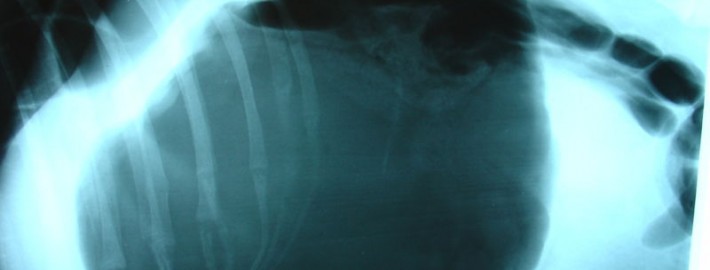

Les signes cliniques de torsion gastrique sont facilement identifiables – le chien fait des efforts de vomissements, mais ces efforts sont improductifs – rien ne sort. L’animal présente une salivation importante, une distension abdominale et des signes de douleur. Puis, on note un abattement qui s’aggrave rapidement. Dès que les premiers signes sont observés, il est impératif de se rendre d’urgence chez un vétérinaire. Le diagnostic est facilement confirmé par l’examen physique et la prise de radiographies abdominales.